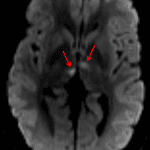

- Small areas of hypoattenuation in both thalami

- Artery of Percheron infarct

Small areas of hypoattenuation in both thalami represent age-indeterminate infarcts. Recommend brain MRI for further evaluation. No evidence of acute hemorrhage, mass effect, or hydrocephalus.